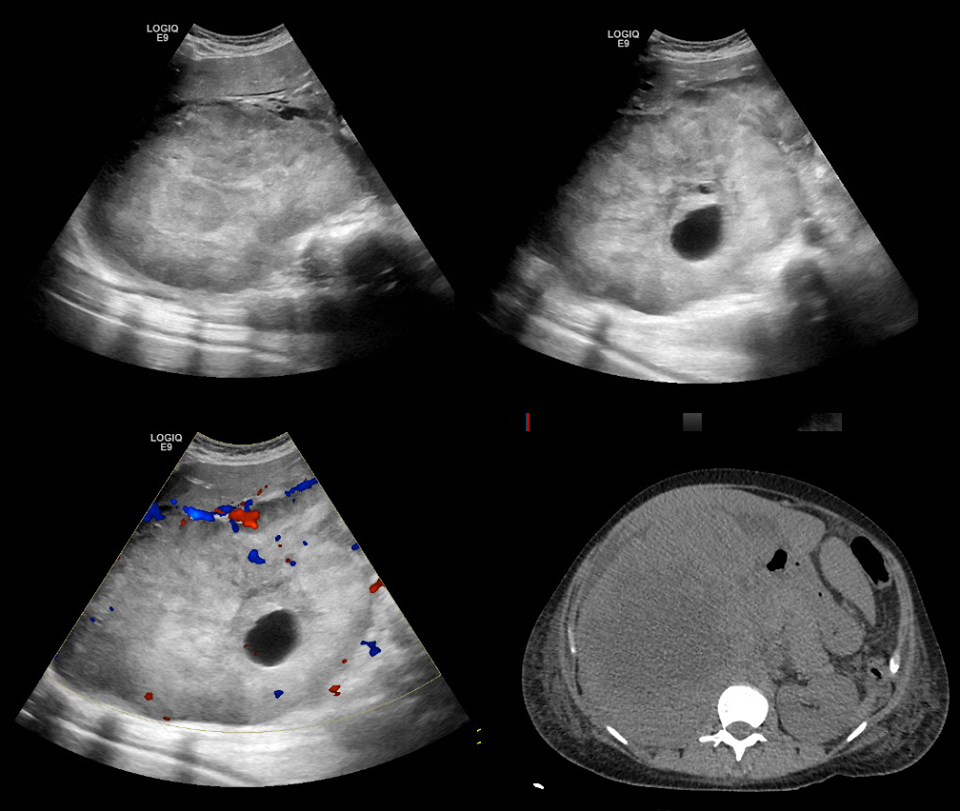

RMN de cráneo mostró tejido blando anormal a lo largo de las paredes anterior y lateral del seno esfenoidal izquierdo, en el vértice de la órbita izquierda extendiéndose posteriormente en el seno cavernoso izquierdo. Este tejido blando era de densidad intermedia tanto en una imagen potenciada en T2 (Figura A) Y una imagen potenciada en T1 con contraste (Figura 1B). Una imagen de RMN con contraste, coronal (Figura 1C) mostró aumento anormal en la unión del seno cavernoso y la cavum de Meckel en el lado izquierdo, con realce de tejido que se extendía a la parte interna del foramen oval.

Figura 1

Estudios por imágenes de los senos paranasales y órbitas.

RMN DE ÓRBITAS REALIZADA EN OTRO HOSPITAL. Una imagen en T2 (Panel A)y una T1 con contraste (Panel B) muestra tejido de densidad intermedia tapizando el seno esfenoidal y afectando el vértice de la órbita izquierda y el seno cavernoso (flechas). Un corte coronal en T1 (Panel C) muestra realce de partes blandas extendiéndose inferiormente al foramen oval. Una TC de órbita (Panel D) muestra que el hueso entre el seno esfenoidal y el vértice de la órbita están relativamente intactos a pesar de la presencia de tejido con densidad de partes blandas anormal a ambos lados (flecha).

TC de las órbitas (Figura 1D) reveló que el hueso entre el tejido blando anormal en el seno esfenoidal izquierdo y el tejido blando anormal en el vértice de la órbita izquierda estaba prácticamente intacto.